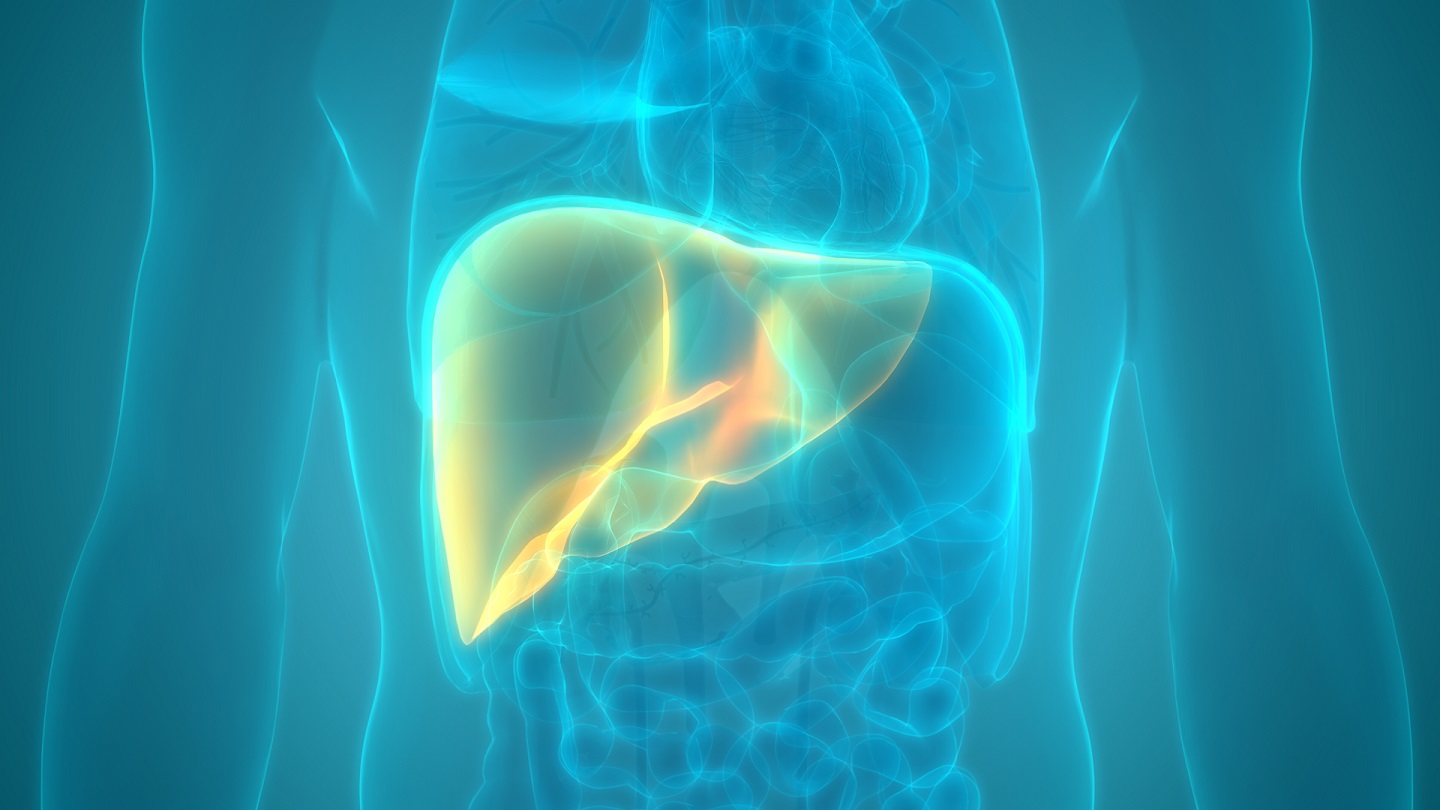

Liver Health Fact from Fiction

Navigating liver health can be challenging. Countless products tell you they can help “cleanse” your liver to keep it healthy, particularly following a period of overindulgence. Hey, it’s nice to have a backup plan if you’re planning on drinking too many beverages or taking back a tub of ice cream, right? But let’s get real ...click here to read more